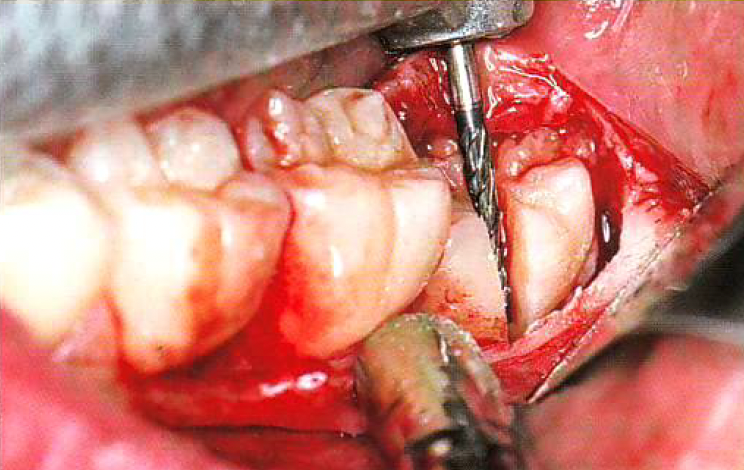

Les extractions simples deviennent rapidement complexes lorsqu’on manque d’outils, de vision ou de stratégie. Cette formation de 3 jours, donnée par un chirurgien maxillo-facial, est conçue pour les dentistes qui veulent passer au niveau supérieur et aborder les cas difficiles avec précision, confiance et maîtrise.

Et pour rendre l’apprentissage encore plus concret, vous pourrez amener jusqu’à deux de vos propres patients et réaliser la chirurgie de votre choix sous supervision directe. Une occasion unique de pratiquer, de progresser rapidement et d’intégrer immédiatement ces compétences à votre réalité clinique.